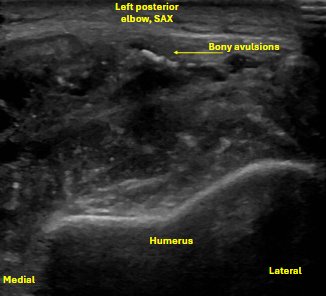

Unlabeled short axis view at the level of the distal humerus proximal to the olecranon fossa, evaluating the triceps tendon/muscle with evidence of bony avulsions.

Labeled short axis view of the distal triceps tendon stump showing loss of normal fibrillar structure of the triceps tendon, with discrete bony avulsions within the retracted triceps tendon. There is anechoic and hypoechoic fluid signal, compatible with hematoma or seroma formation.